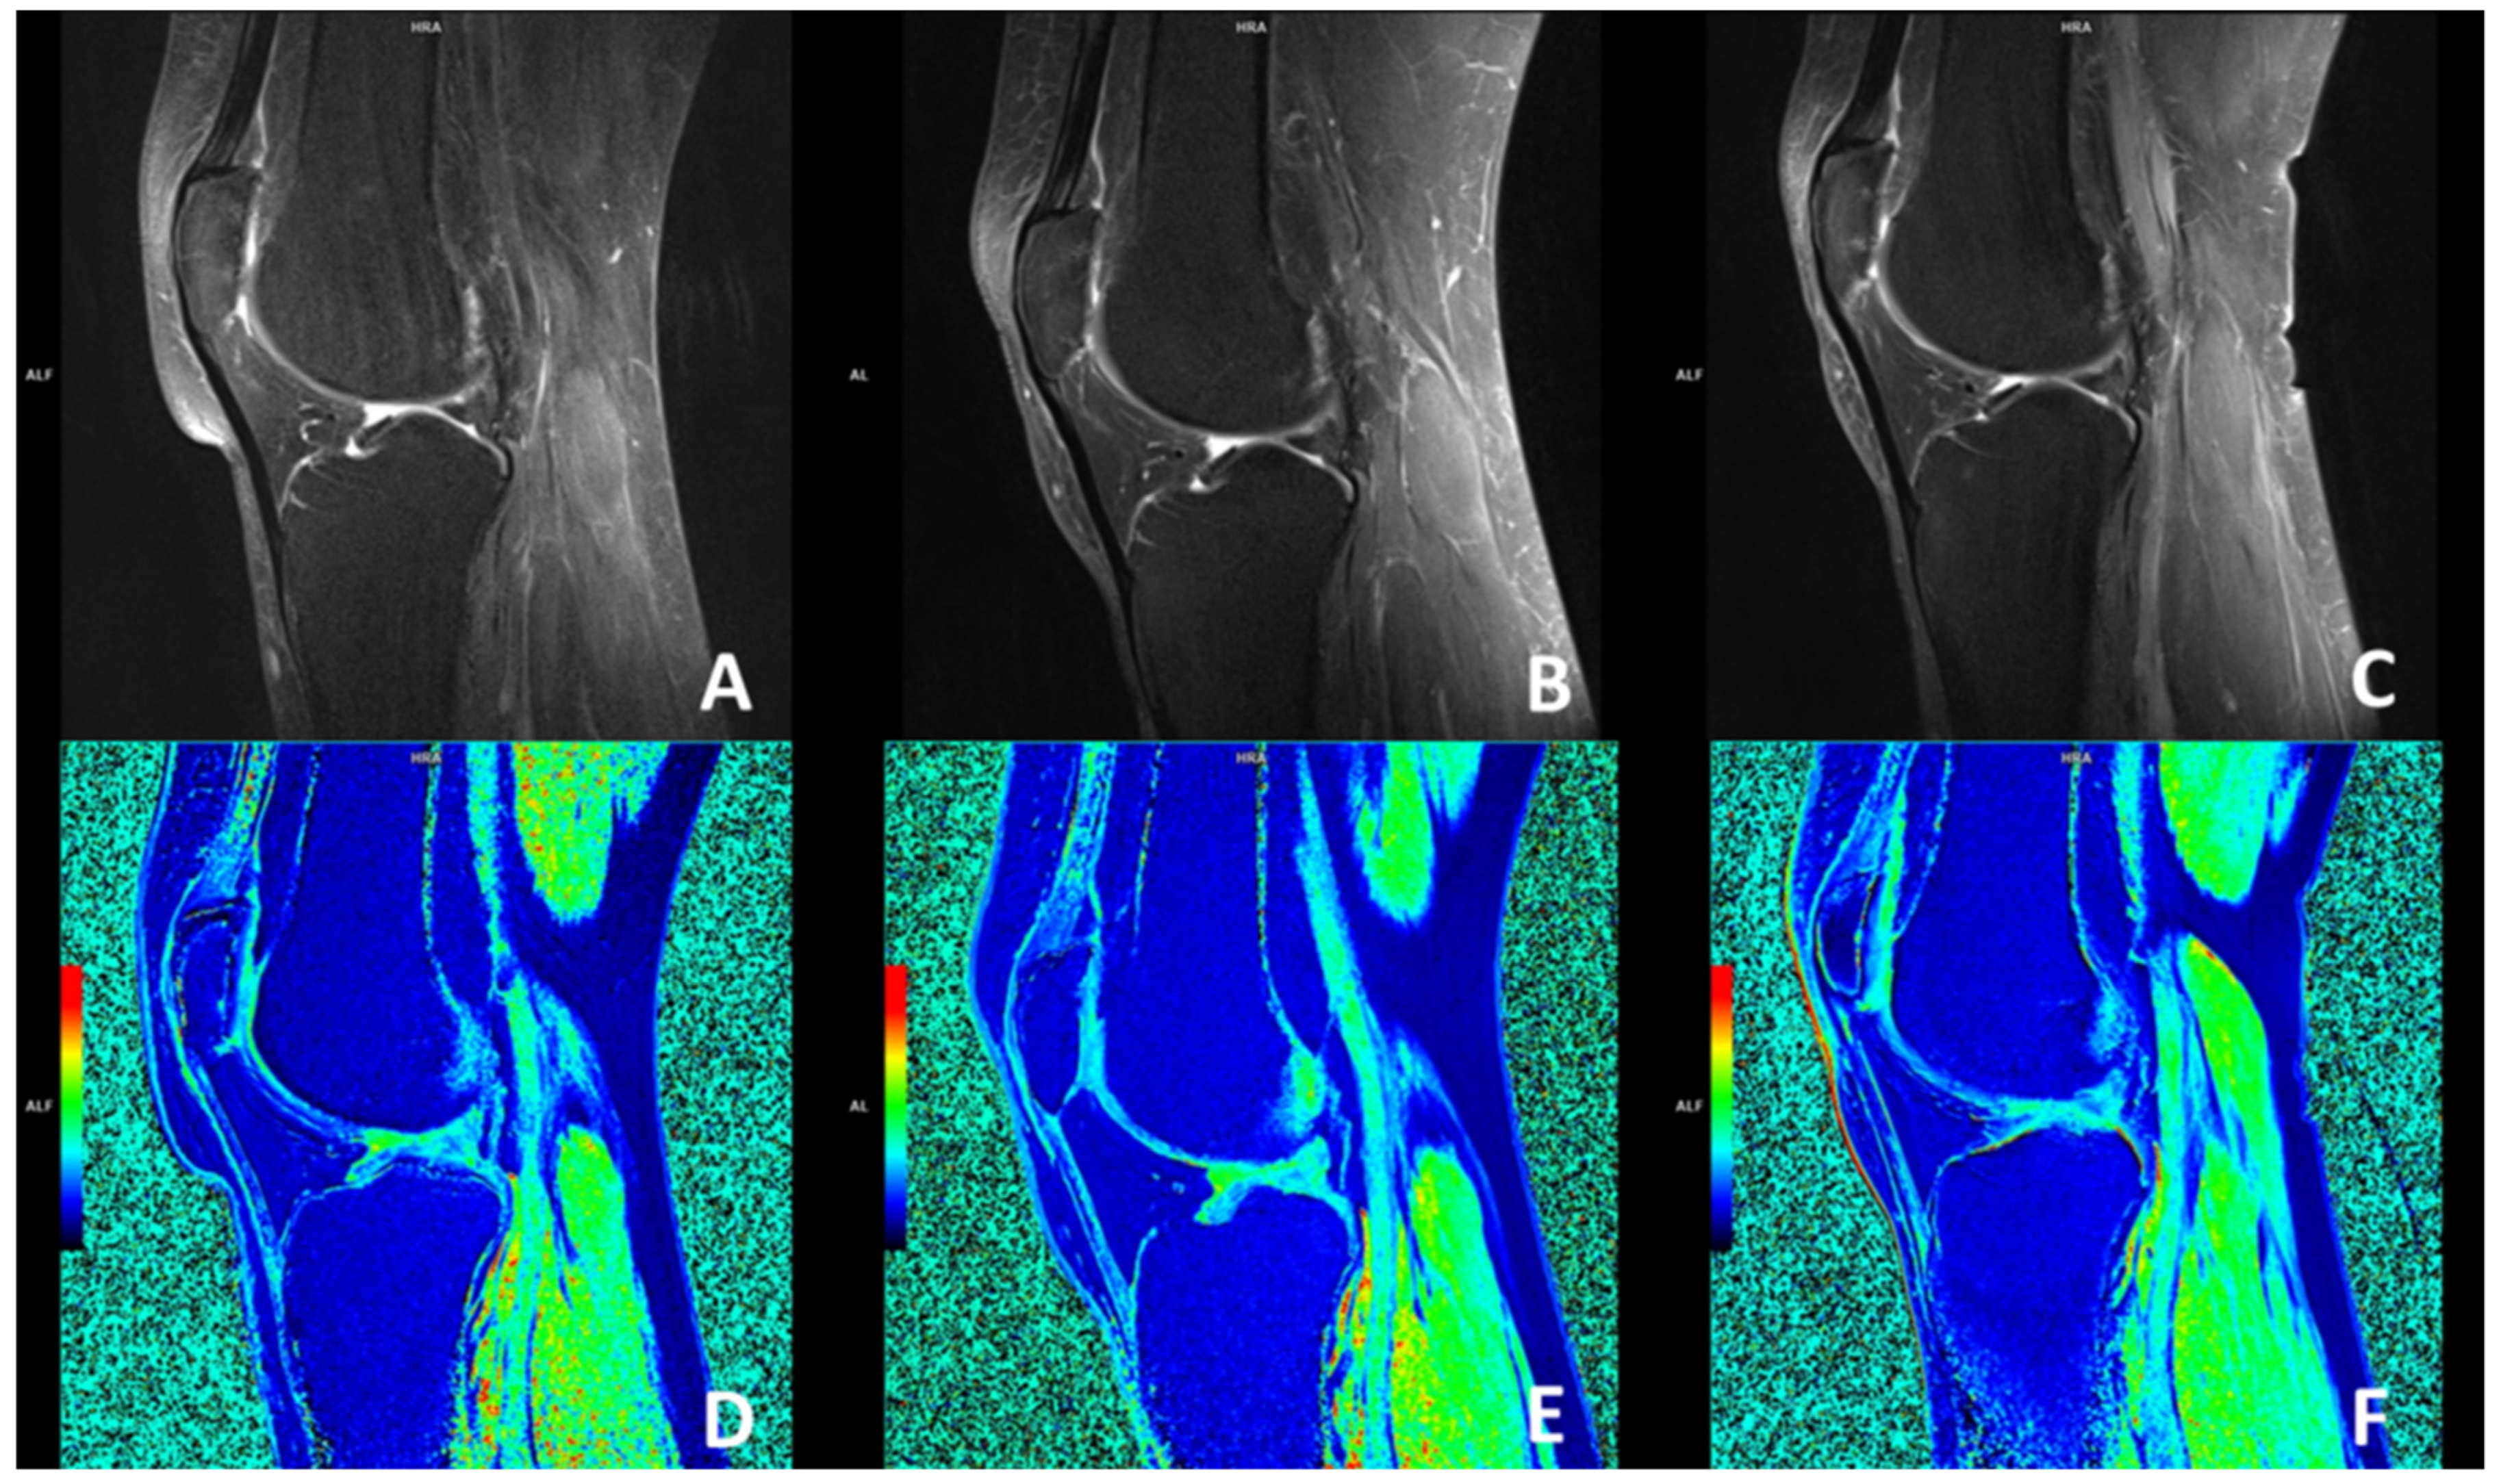

The magnetic resonance imaging using the dGEMRIC index showed no significant improvement in the glycosaminoglycan (GAG) composition of the cartilage in the knees treated with ACA-SVF and LP-PRP at 3- and 6-month follow-ups when compared to the baseline values for each of the analyzed compartments, including medial and lateral femur, medial and lateral tibia, trochlea, and medial and lateral patella (Figure 4).

Sagittal MRI magnetic resonance imaging (MRI) slices through the center of the knee accessing the patellofemoral joint osteoarthritic changes using fat-suppressed proton-density-weighted turbo spin-echo method at baseline (A), 3 months (B), and 6 months (C) follow-ups with corresponding delayed gadolinium-enhanced MRI of the cartilage (dGEMRIC) images (D–F). No changes were seen when dGEMRIC indices were calculated.